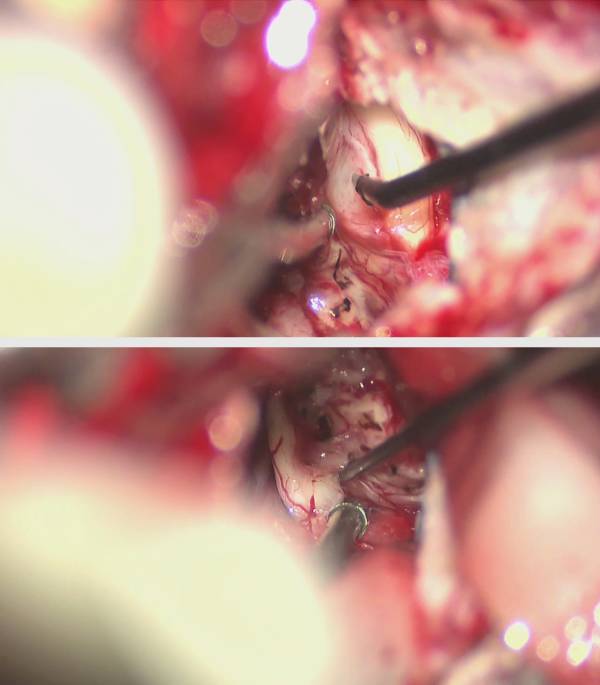

图13. 于肿瘤上极识别并小心松解三叉神经(上图);对于较大肿瘤或已无有效听力的患者,在肿瘤下极经电刺激确定蜗神经后可将其切断(下图)。

图14. 逐步将面神经从肿瘤的前下表面分离出来。